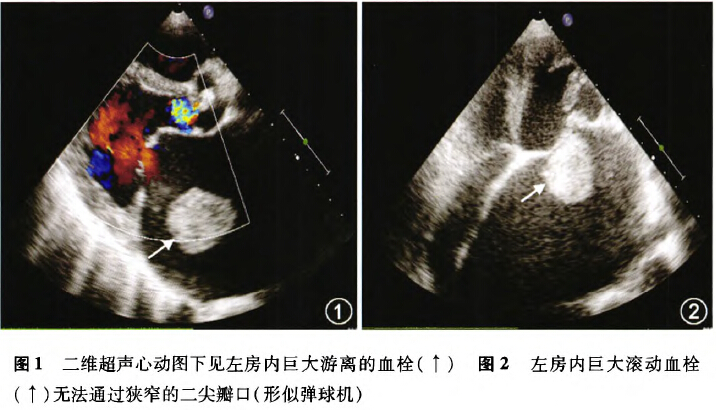

超声心动图上的